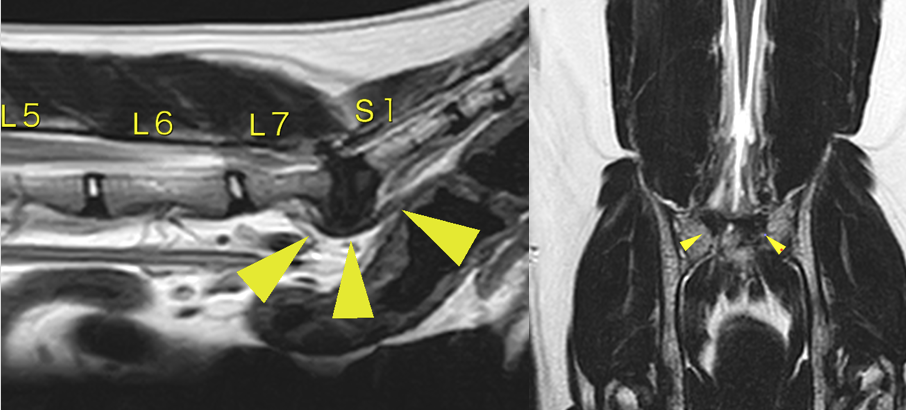

近年では猫のDLSS(馬尾症候群)が多いと言われるようになりました。年をとった猫が増加したのと、MRIの普及により今まで見逃されていたものが見つかるようになったことが考えられます。 猫では犬よりも脊髄が尾側まで走行しており、犬に比べて痛みが強く出たり症状が出てしまうことが多いです。 診断や治療は犬と同様で、MRIにより診断し、手術による治療を行います。

L7-S1の間に圧迫が見られます。矢頭部が圧迫物質です(黄色靭帯の肥厚がメイン)。

背側からラウンドバーと呼ばれる機械で削り、中に見えてくる黄色靭帯を摘出していきます。圧迫が解除されたらスクリューをうち、セメントによって固定します。